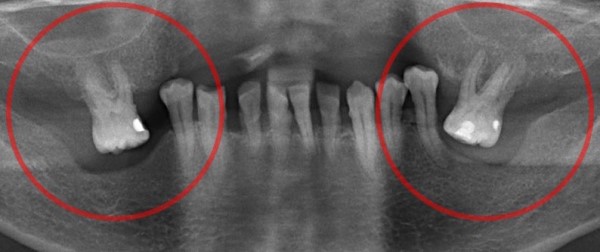

Основной особенностью феномена Попова-Годона является то, что антагонисты потерянных единиц начинают выдвигаться вертикально, входя зазор, образовавшийся в результате адентии. Количество выдвигаемых зубов зависит от размера дефекта и может достигать 4-х.

Основное проявление феномена состоит в том, что зубы, расположенные напротив дефекта, выдвигаются вертикально, заполняя собой образовавшуюся вследствие адентии пустоту. Иногда выдвижение бывает таким значительным, что они достигают слизистой оболочки десны в месте отсутствующих зубов.

Зубы, расположенные рядом с дефектом, также меняют свое местоположение; могут поворачиваться вокруг оси, наклоняться в любую из сторон (вертикально, дистально, мезиально, в язычном и вестибулярном направление или в виде комбинации нескольких перемещений). Патологическая перестройка начинается от дефекта и распространяется затем на весь ряд.

Выраженность деформаций зависит от множества факторов – количества потерянных единиц, протяженности и локализации дефекта, состояния интактных зубов, типа прикуса, времени, прошедшего с момента утраты зубов, состояния здоровья пациента и его возраста. У детей синдром Попова-Годона развивается намного быстрее, чем у взрослых.